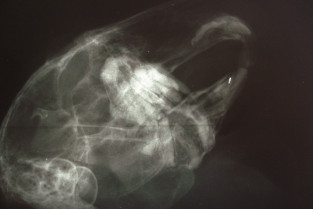

La dentisterie du lapin